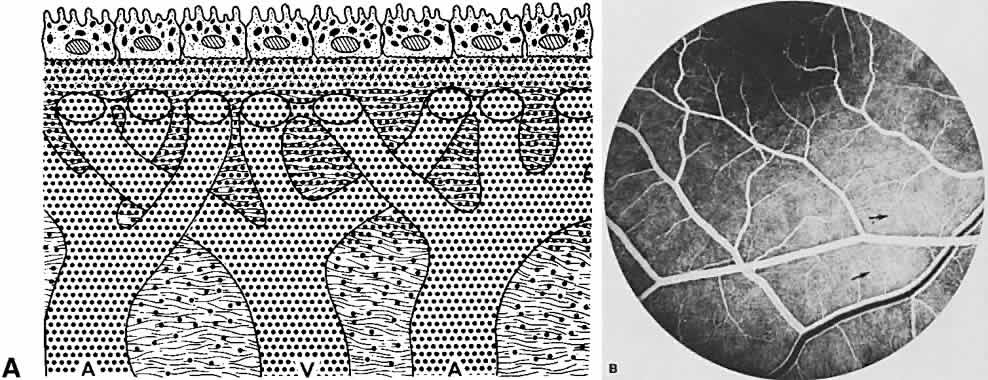

The RPE also functions as an optical barrier because of the presence of pigmented melanosomes (Fig. 6). The density of this pigment varies with retinal location; it is greatest in the foveomacular region and least anterior to the equator. There are more pigmented epithelial cells per unit area in the foveomacular region than in the periphery. Posteriorly, the cells are tall and columnar, with several layers of melanosomes crowded together. Anteriorly, the cells gradually become flatter and more cuboidal, with a corresponding loss of relative pigment concentration (Fig. 7). In any normal eye, regardless of the comparative fundus color, the greater pigmentation in the foveomacular area gives this zone a darker clinical appearance when compared with the remainder of the posterior pole and periphery.

Fig. 7. Relative difference in morphology of RPE. Assuming that each RPE cell has approximately the same number of melanosomes, then the pigment density is a function of height and width of the cells. The RPE in the foveomacular area are tall and columnar shaped in contrast to the more cuboidal RPE cells in the surrounding posterior pole. The greater density of pigment in the columnar cells helps to explain the foveomacular dark spot seen in this normal fluorescein angiograph.

Each patch appears to fill evenly and is the result of separate, irregular areas of choriocapillaris supplied by larger choroidal vessels at slightly different times. The background choroidal flush gradually intensifies and spreads anteriorly toward the ora serrata. The entire choroidal sequence is obscured in the foveomacular area because of the denser pigmentation in the overlying RPE, and possibly the increased amount of xanthophyll in the sensory retina (see Fig. 7).16 To observe the larger choroidal vessels fill with fluorescein, attention must be focused deep to the RPE very early in the study, before the choroidal flush quickly masks these feeding vessels (see Figs. 7, 11B, 12B, 13B, and 14B). As the fluorescein enters the intravascular system of the choroid, it immediately leaks into the extravascular space (see Fig. 12A). This leakage is related to the capillary fenestrations seen in the choriocapillaris. Leakage of fluorescein in the choroid is most intense directly below Bruch's membrane and in the inner choroidal layers (see Fig. 13A). Diffusion then occurs throughout the entire extravascular space to eventually involve the inner scleral fibers (see Fig. 14A). The concentration of fluorescein rapidly equilibrates throughout the inner choroidal layers in both the intravascular and extravascular compartments. The concentration in the extravascular stroma of the outer choroid is probably less. This occurs during the filling phases of the study, usually by the venous phase of the retinal circulation (see Fig. 14). As the study progresses, fluorescein continues to leak from the choroidal vessels. Concurrently, (the density of fluorescein within the vessels becomes less because of the extravascular leakage and dilution by equal distribution throughout the entire blood volume. Therefore, the concentration of fluorescein within the choroidal vessels rapidly becomes less than that in the extravascular choroidal tissue. This occurs in the inner choroidal layers first and can be recognized as the medium-sized choroidal vessels begin to appear as silhouettes against the more concentrated extravascular fluorescence (Fig. 15).